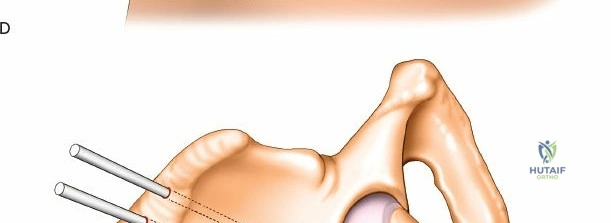

Wrist Spanning External Fixation

Wrist spanning fixators are the workhorse for highly comminuted distal radius fractures or radiocarpal fracture-dislocations.

Metacarpal Pin Placement

1. Make two 1 cm incisions over the dorsoradial aspect of the second metacarpal.

2. Dissect bluntly, protecting the dorsal sensory branches of the radial nerve and the extensor tendons.

3. Place the tissue sleeve at a 45-degree angle to the dorsal and lateral planes to maximize purchase in the metacarpal shaft.

4. Pre-drill and insert two 3.0 mm pins.

Proximal Radius Pin Placement

1. Make incisions over the dorsolateral aspect of the radius, approximately 10-12 cm proximal to the radiocarpal joint.

2. Dissect bluntly to avoid the SRN.

3. Insert two 4.0 mm pins.

Construct Assembly and Reduction

Connect the metacarpal pins and the radius pins with a multi-pin clamp or individual pin-to-bar clamps. Apply longitudinal traction to utilize ligamentotaxis to restore radial length and radial inclination. Volar tilt is often restored by translating the distal fragment or applying a slight volar directed force before tightening the frame. Confirm reduction with PA and lateral fluoroscopy.